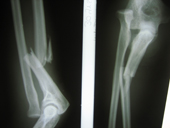

| Monteggia fracture preop |

Monteggia fracture post op |